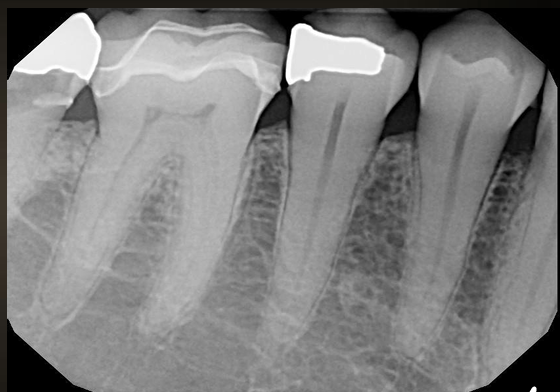

what do these images have?

interproximal caries (not incipient)